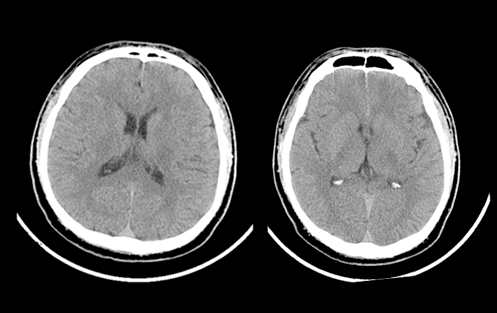

臨床圖像